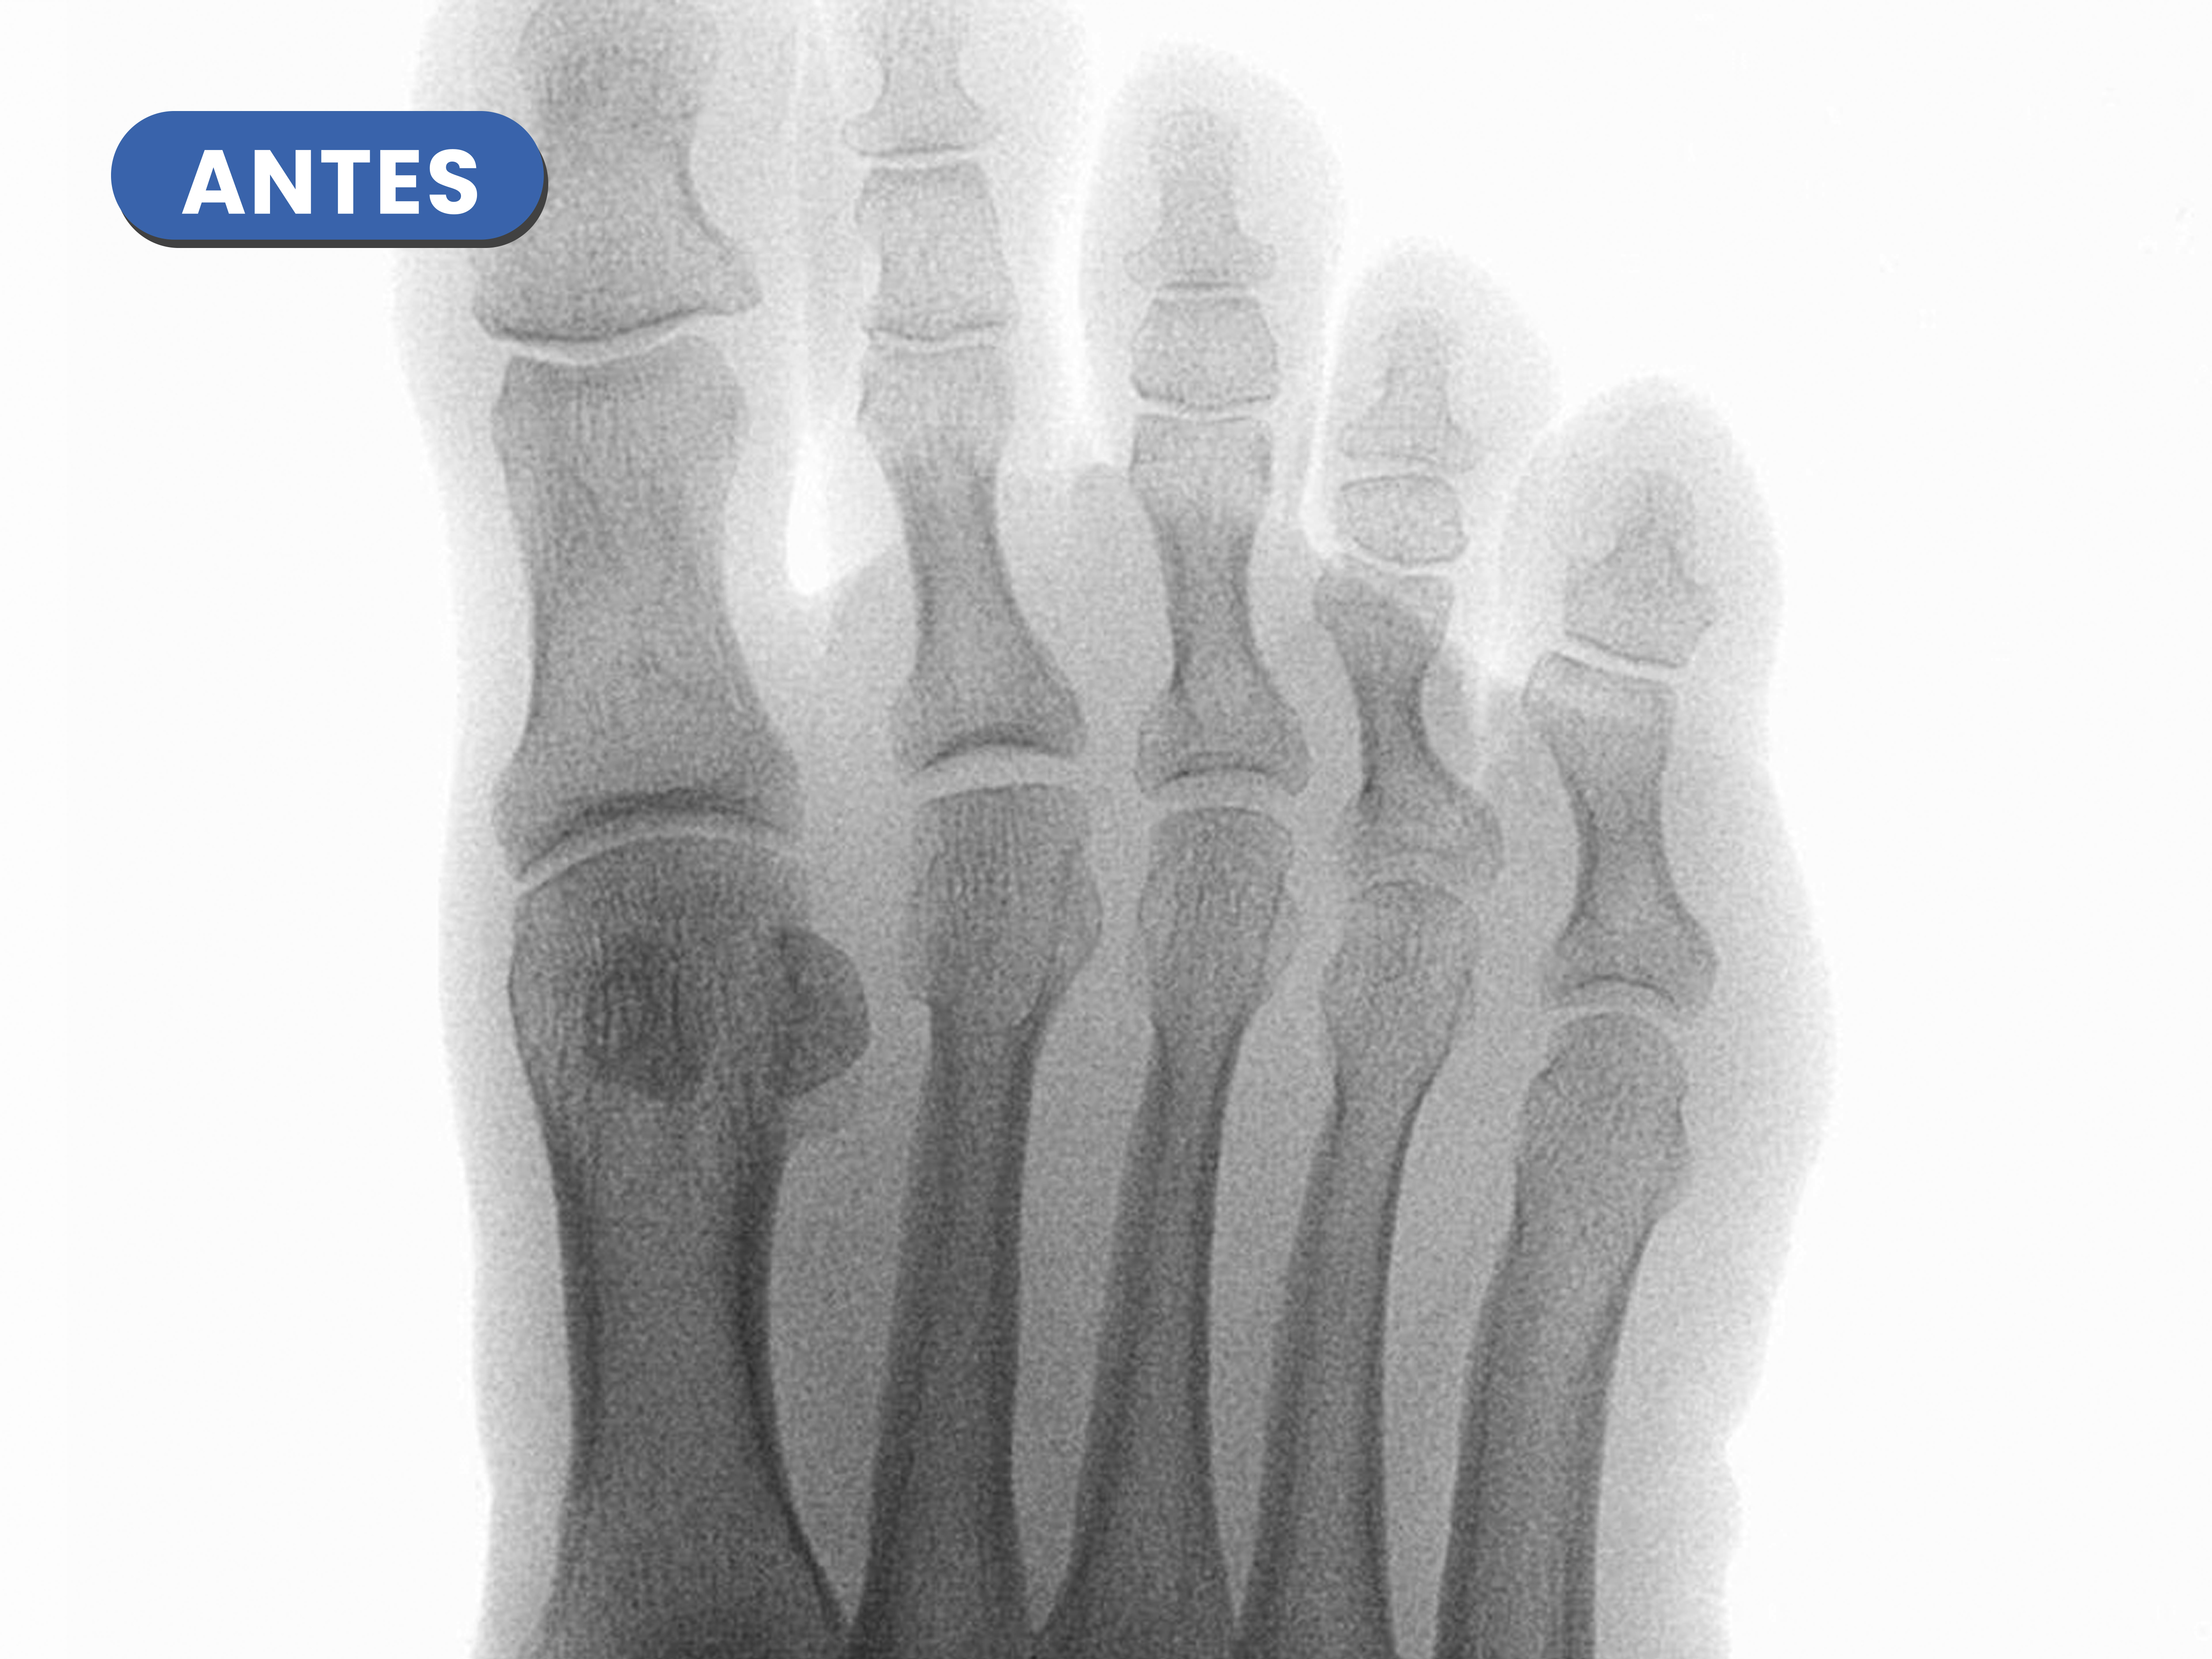

Casos reales resueltos con Cirugía de Mínima Incisión (CMI)

Te mostramos casos reales resueltos mediante cirugía de mínima incisión por el Dr. Rubén Lorca y su equipo.

Mueve las flechas para visualizar el antes y después.

En la radiografía previa a observamos la hipertrofia en la base de la falange distal y la cabeza de la falange proximal como desaparece tras el limado con la fresa.